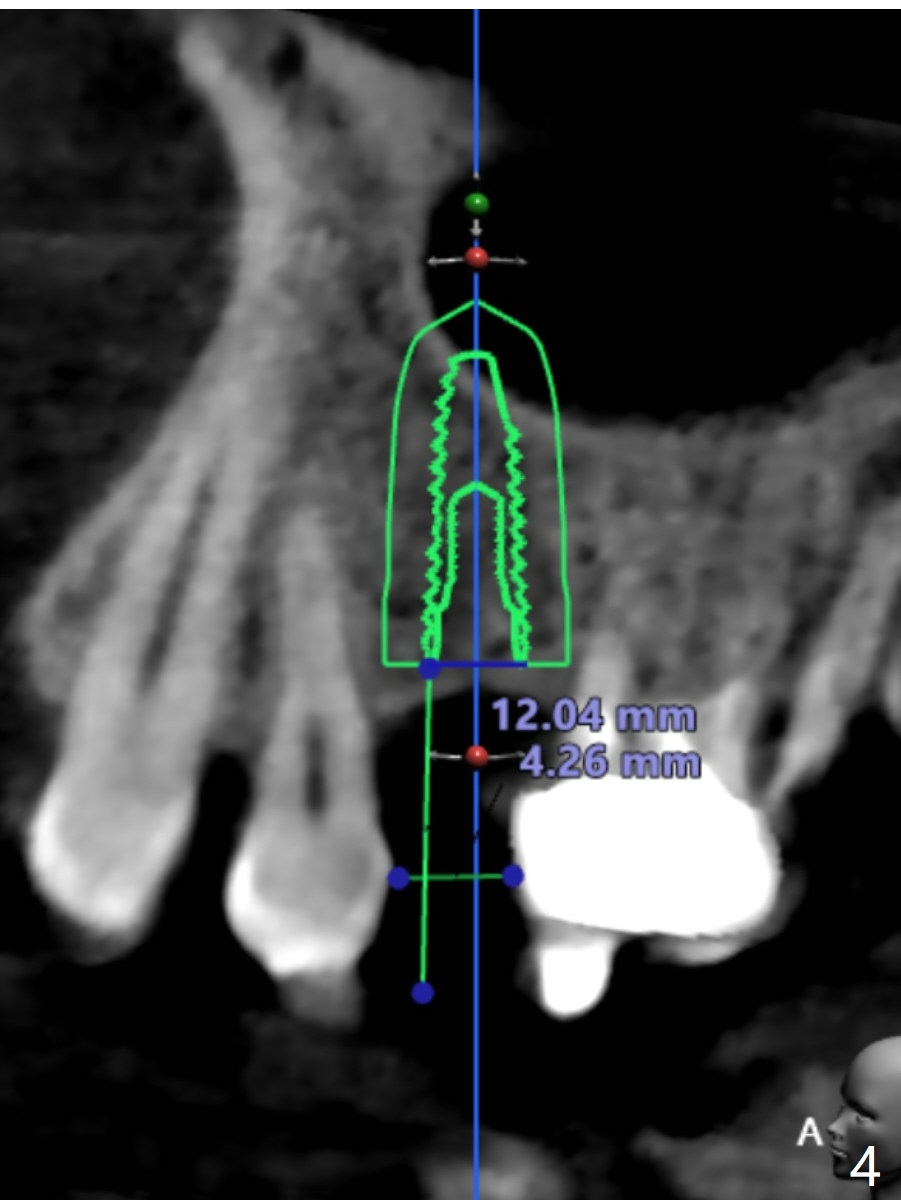

A 54-year-old man has lost a crown at #15 due to root fracture. The latter is associated with bruxism and missing #13. He agrees to have 2 implants and limited ortho to increase the space at #13. In fact the space increases by proximal reduction before CT and impression for guide (Fig.1). The space is enough for a narrow metal sleeve (Fig.4). To prove that abutment screw loosening is most likely related to implant trajectory, IBS implants (with history of easy screw loosening) will be placed with the help of IS guide. PRF will be prepared (x2), one for sinus lift and the other for palatal plate repair. Take photos for palatal fistula.